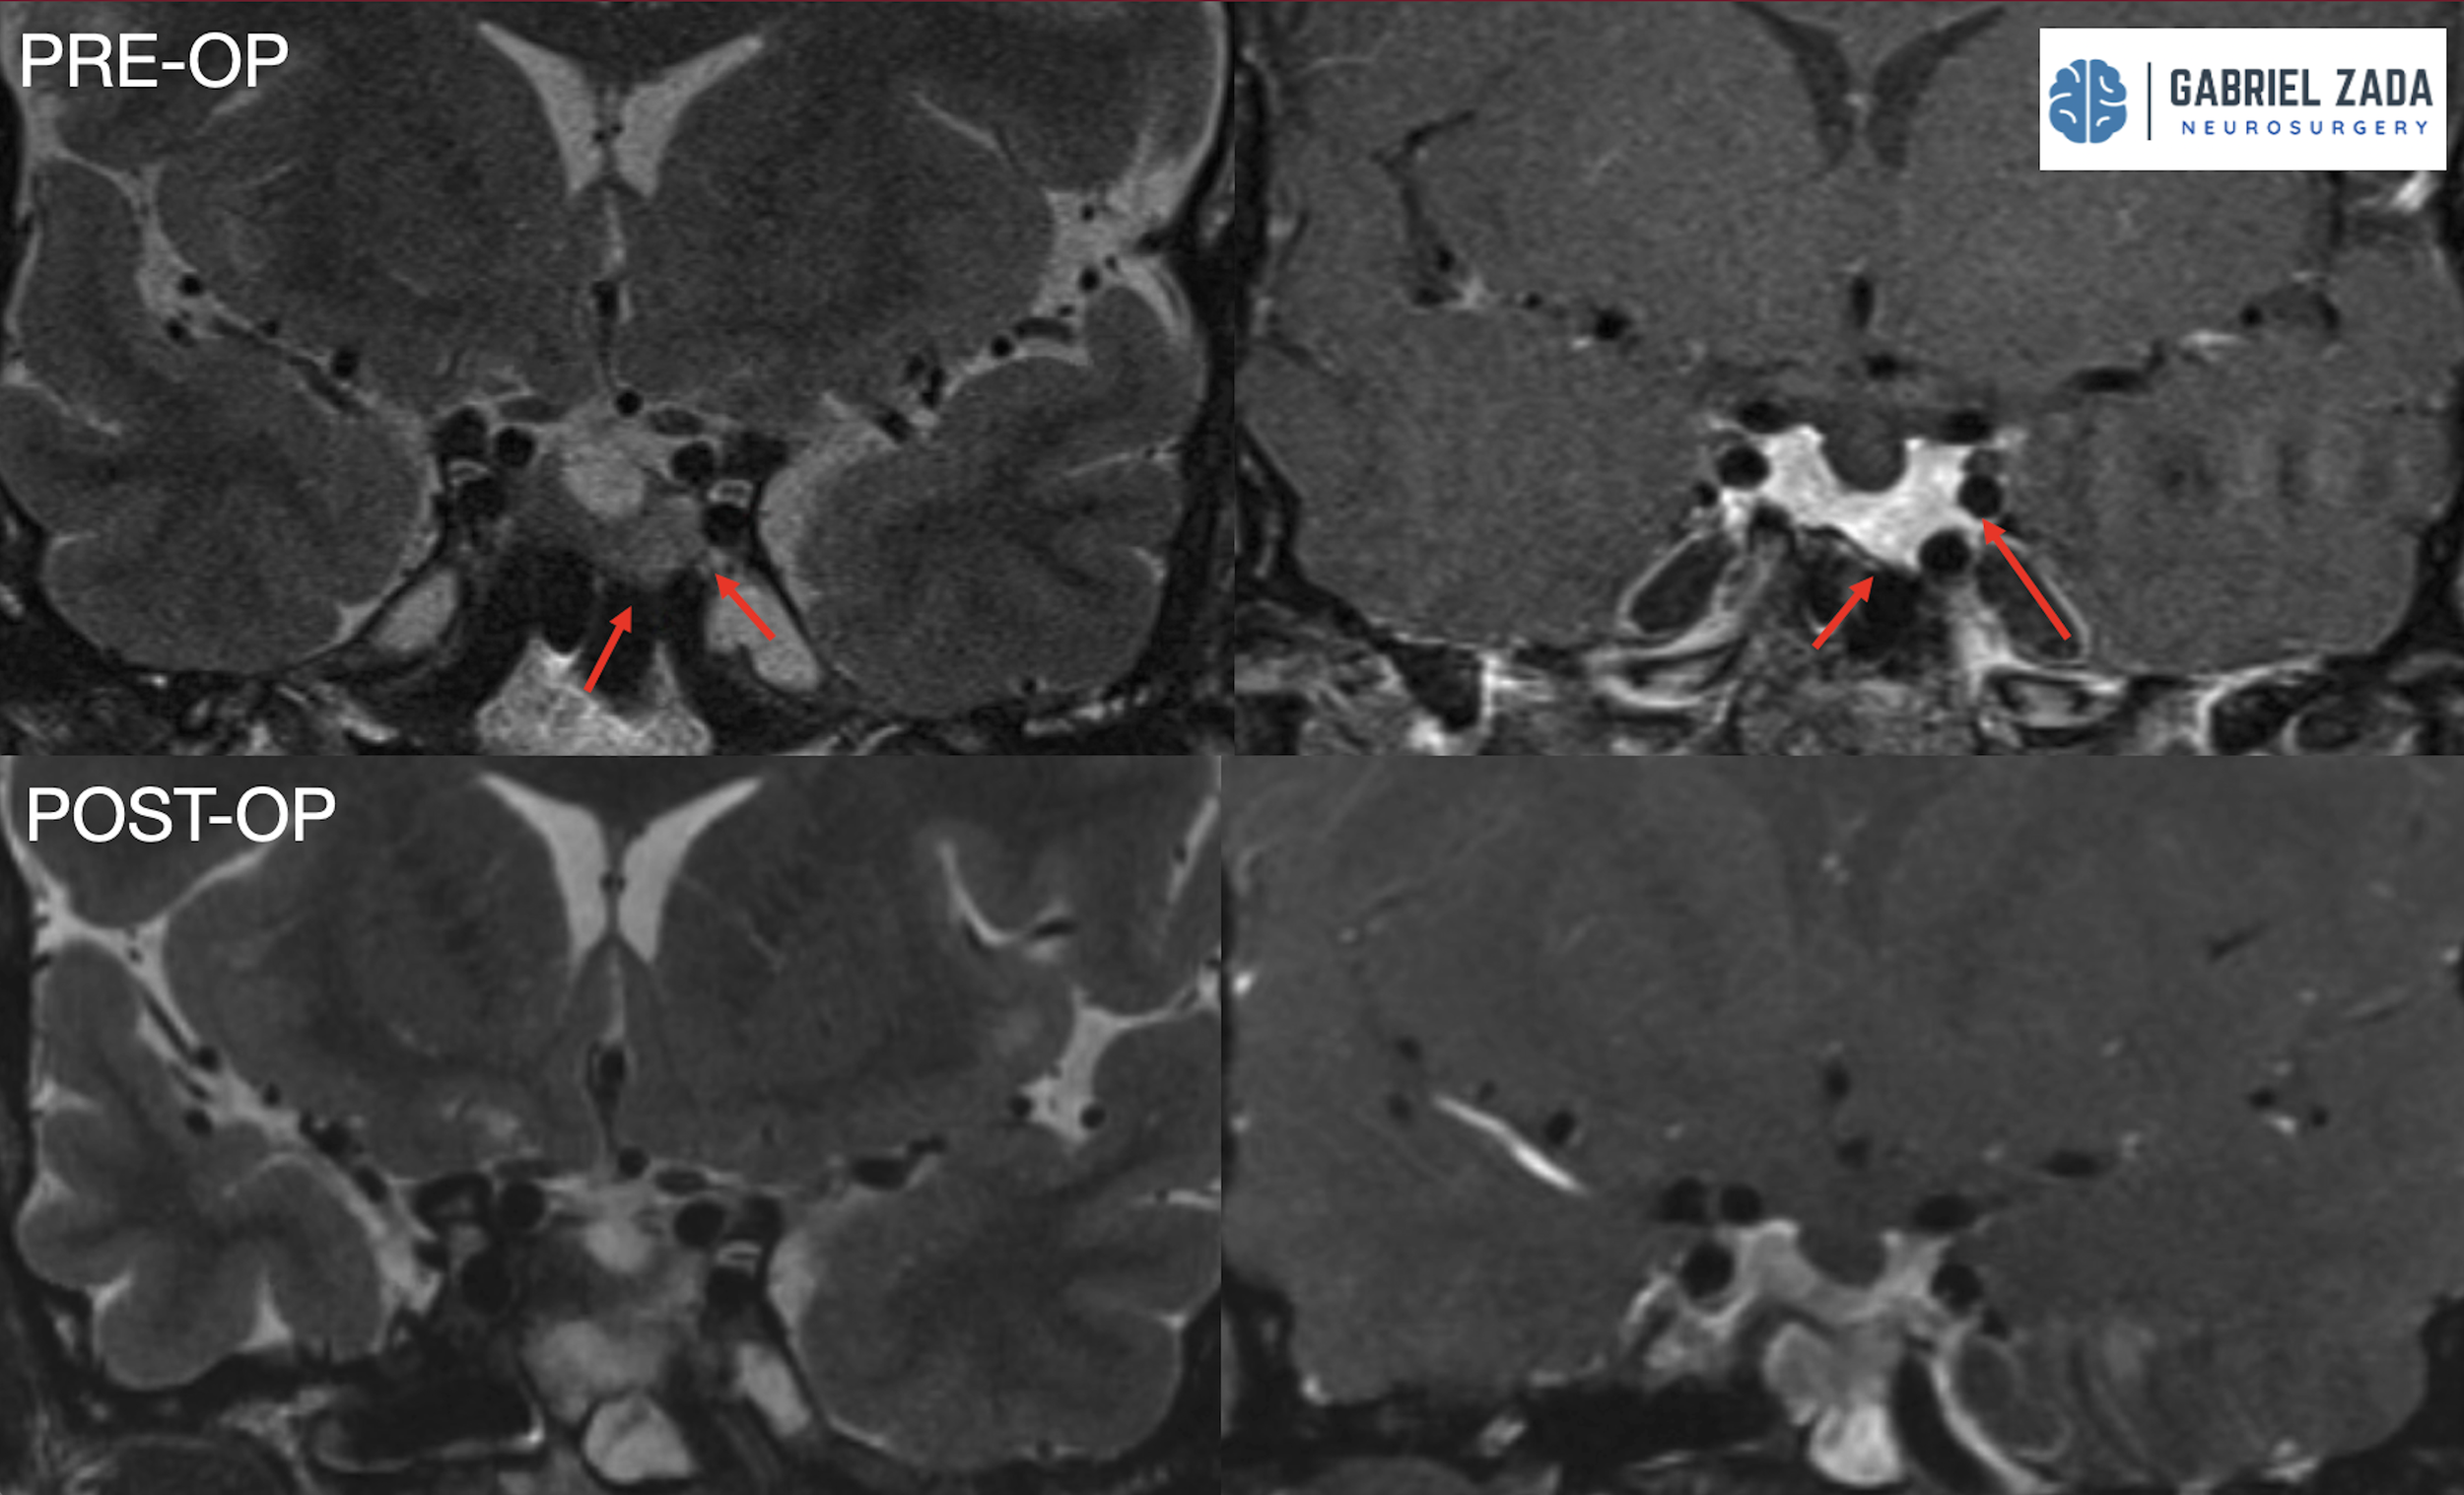

Explore this comprehensive gallery featuring pre‑ and post‑operative imaging of patients with skull‑base tumors treated by Gabriel Zada, MD, MS, FAANS, FACS. These cases highlight Dr. Zada’s expertise in advanced neurosurgical techniques and outcomes.

*Representative cases shown for educational purposes. All images de-identified. Individual results vary.